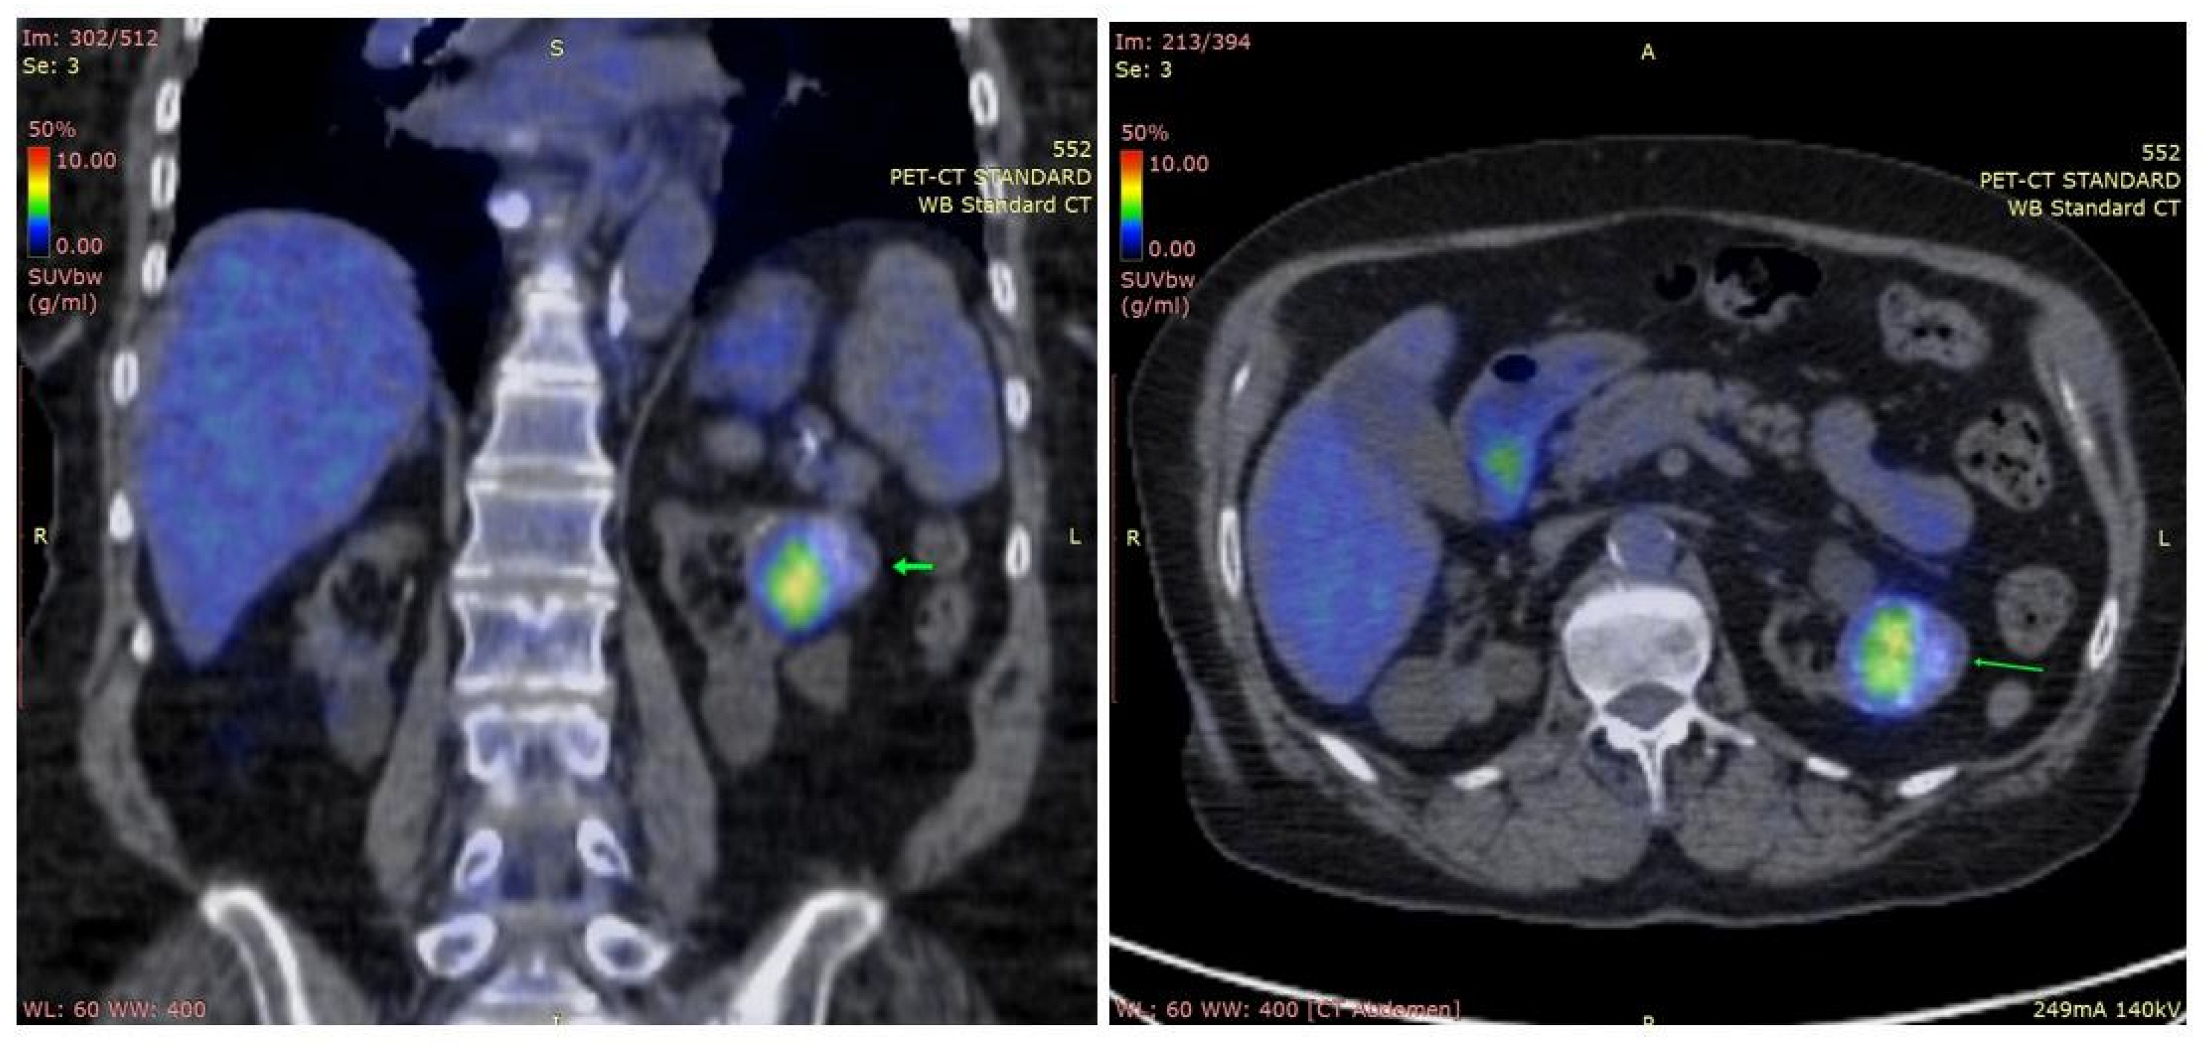

2.1. Case 1